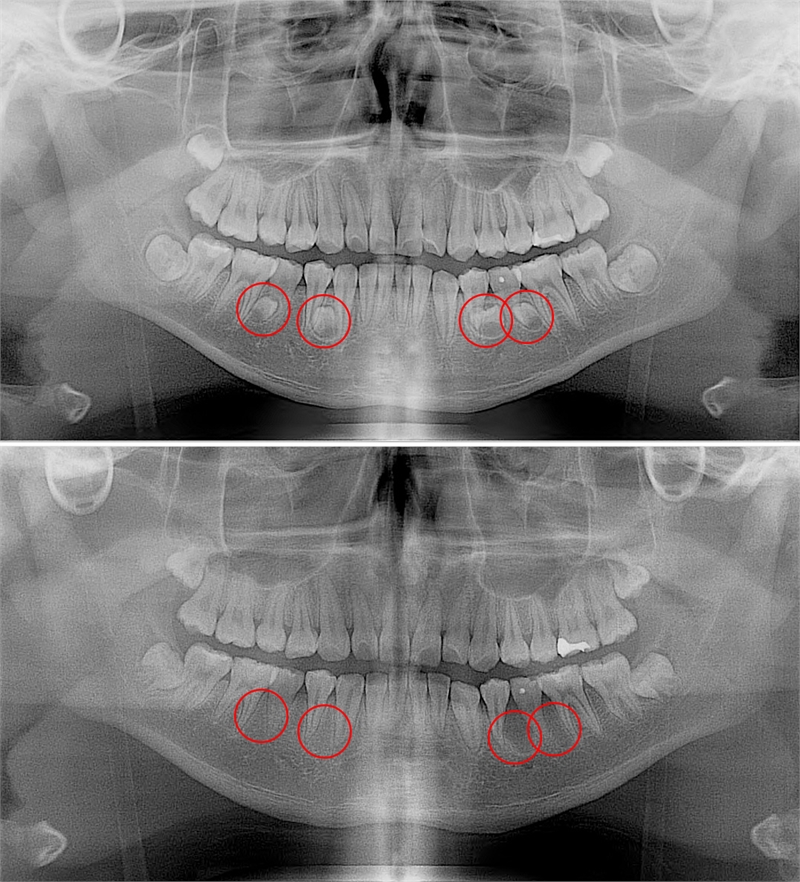

과잉치가 발생하는 정확한 원인은 밝혀지지 않았다. 다만 부모나 형제에게 과잉치가 있으면 발생 확률이 높아지는 것으로 보고 있다. 대부분이 턱뼈 내에 매복돼 있기 때문에 당사자 또는 보호자가 미리 알기는 매우 어렵다. 파노라마 방사선 촬영과 근단 방사선 사진 촬영, CT 촬영 등을 통해서만 발견할 수 있다.